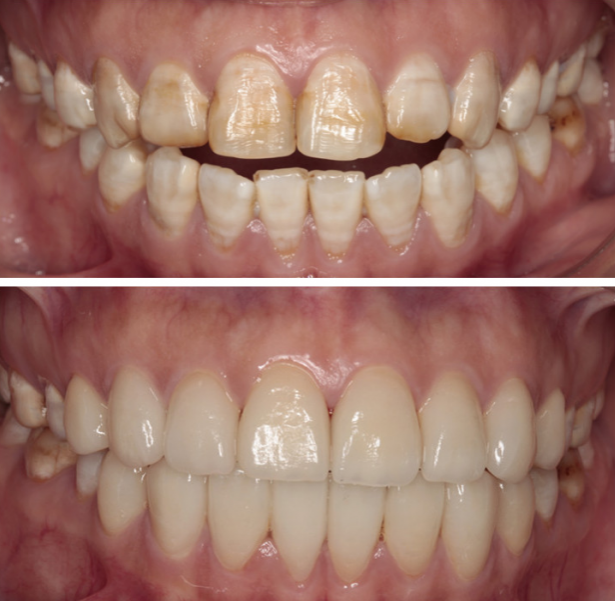

· 牙齿美白(漂白): 通过药物美白,能有效淡化氟斑牙的颜色,改善轻中度的着色。

2. 针对中重度氟斑牙:

· 树脂渗透术: 一种微创技术,用透明树脂渗入多孔釉质,有效遮挡白垩色斑,效果自然。

· 牙齿贴面: 在牙齿表面粘贴一层薄薄的瓷或树脂贴面,能完美覆盖任何颜色的斑块和轻微缺损,效果显著。